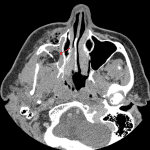

- Herniation of retroantral fat through the posterior wall of the right maxillary sinus

- Right maxillary hemosinus

Herniation of retroantral fat through the posterior wall of the right maxillary sinus. Right maxillary hemosinus.